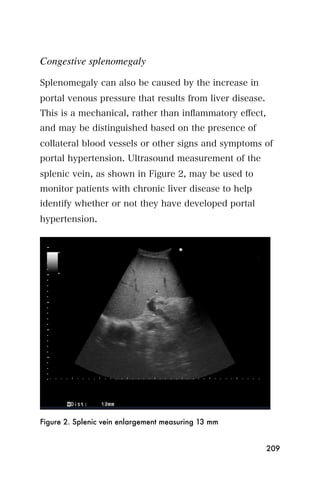

• Kidney stones

• Kidney size may suggest pathology

• Kidney masses, tumors or cysts

• Polycystic kidney disease